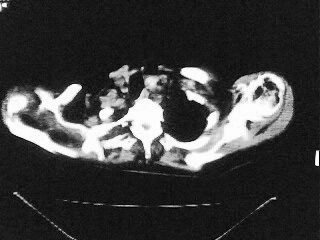

以下是引用随光逐影在2009-2-10 0:07:00的发言:[br]1)右肺放射性肺炎并节段性肺不张?请结合相关病史。2)右侧胸膜肥厚、粘连。3)心包膜增厚(或心包少量积液)。